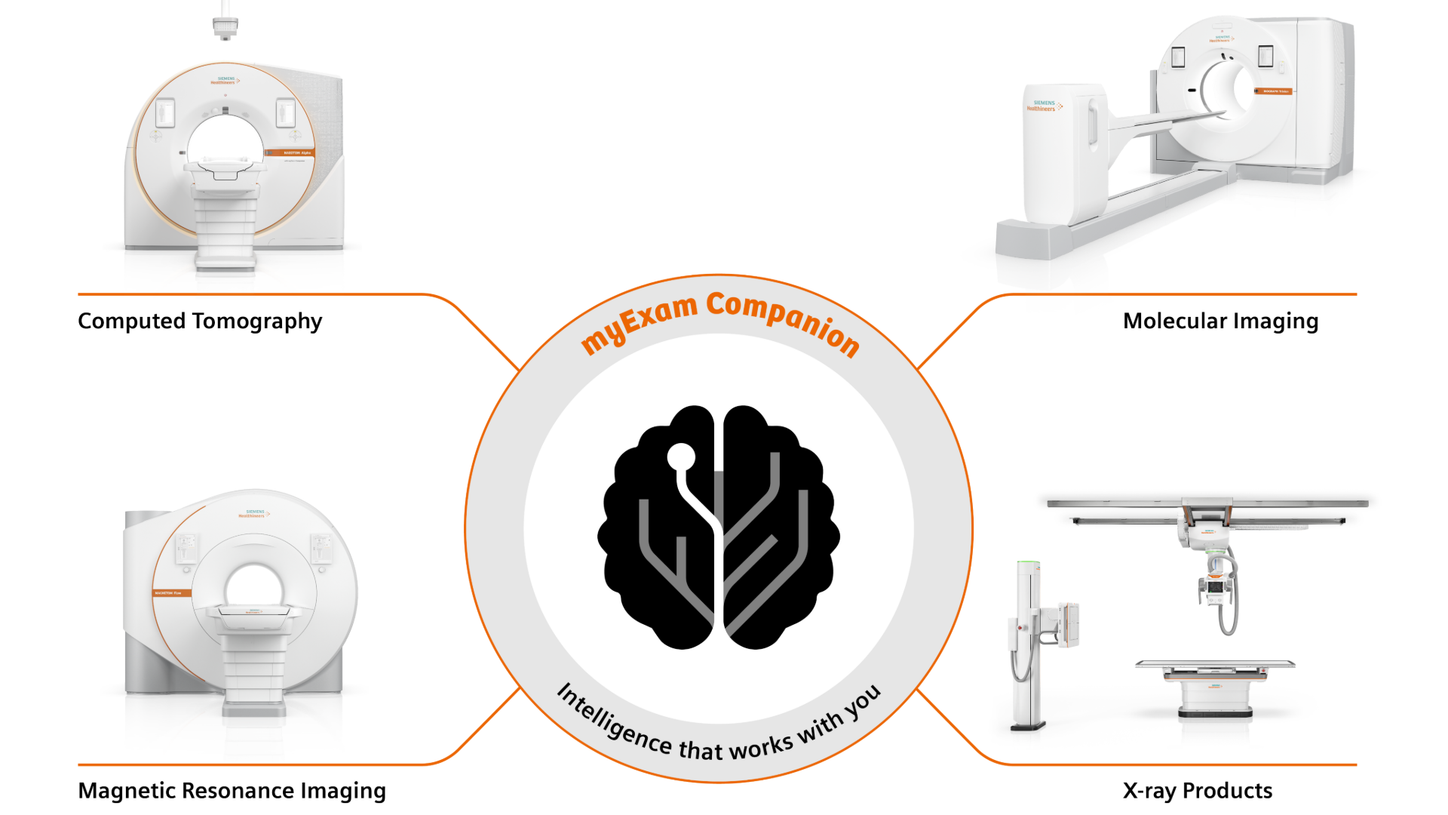

We are empowering decision making for technologists, radiologists, and clinicians along the whole imaging value chain and making it even smarter – allowing healthcare professionals to make the right decision at the right time within the patient pathway. Our AI-powered solutions are not just tools but essential allies in the modern medical imaging landscape, designed to increase productivity, improve clinical precision, and be integrated seamlessly.

Along the imaging pathway there are plenty of levers for productivity and clinical precision

Use seamlessly integrated intelligence to acquire the best images and accelerate your decision making and reporting process through the smart use of data and AI technology. Explore each step within the smart imaging value chain to learn more about our AI portfolio in radiology.